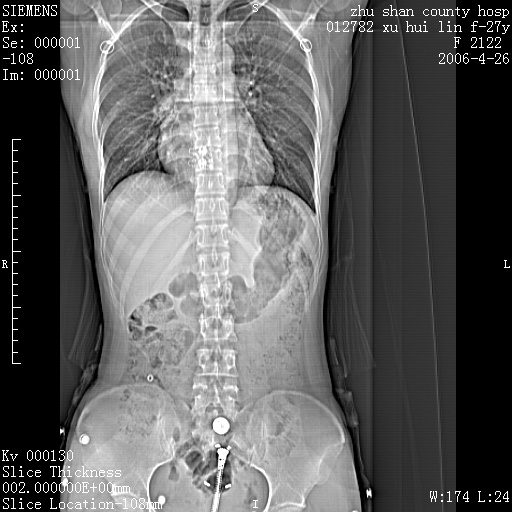

女性 病人 27岁!本院职工家属,五月前因感冒透视发现病变,ct示:左肺下叶背段感染性病变。经过半月规范抗生素治疗后复查病变无明显变化,后行四月规范抗痨治疗,复查无明显变化,后复查无效!请大家帮忙看看!

右肺下叶背段见片状高密度区,边界不清,密度不均,无钙化及空洞影,背段支气管通畅。所见层面肺门及纵隔内未见明显肿大淋巴结影。

女性 病人 27岁!本院职工家属,五月前因感冒透视发现病变,ct示:左肺下叶背段感染性病变。经过半月规范抗生素治疗后复查病变无明显变化,后行四月规范抗痨治疗,复查无明显变化,后复查无效!

诊断:首先还是考虑为慢性炎症。

结核虽然好发于下叶背段,但周围无明显卫星灶,化验结果怎样?